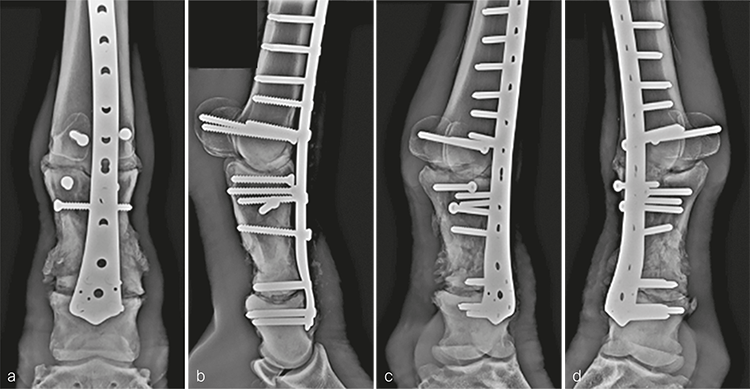

Following recovery from anesthesia, the mare was placed in intensive care for 24 hours to stabilize her physiological status before surgical fixation. Bridging plate fixation of the comminuted P1 fracture in conjunction with arthrodesis of the metacarpophalangeal and proximal interphalangeal joints was accomplished using an LCP DFP (11-holes). Prior to fixation, articular cartilage was debrided from the articulations using a 4.5 mm drill bit and curettes passed through stab incisions. The frontal plane fracture in the proximal aspect of P1 was reduced and stabilized with 5.5 mm cortex screws placed in lag fashion from dorsal to palmar in a slightly distal to proximal orientation.

The plate was contoured to the desired 15 of dorsiflexion at the level of the fetlock joint to provide an appropriate joint angle (Fig 4a). Three, approximately 4 cm long dorsal midline incisions were performed through the skin and extensor tendon at the level of the proximal end of the plate, the metacarpophalangeal joint, and at the distal end of the plate overlying the proximal interphalangeal joint. Using a combination of sharp dissection and a large periosteal elevator, a tunnel was created between the bone and overlying soft tissues including the extensor tendon. The plate was inserted into the tunnel and appropriate plate positioning, and cortical alignment were confirmed radiographically. A Push-Pull Reduction Device was placed through hole (A) in the head of the plate at the level of the proximal interphalangeal joint to compress the plate onto the dorsal cortices of the phalanges and maintain alignment of the proximal interphalangeal joint. Five 5.0 mm locking screws were inserted in the expanded head of the plate to purchase the distal aspect of P1 and the proximal aspect of P2. To ensure plate-bone contact proximally, two 5.5 mm cortex screws were placed into the distal aspect of the metacarpus (plate shaft holes 4 and 5). The remaining holes overlying the metacarpus were filled with 5.0 mm locking screws; where possible, 4.5 mm cortex screws were placed through the plate overlying large fragments of the P1. Finally, two 5.5 mm cortex screws were placed in lag fashion abaxial to the plate to engage the medial and lateral proximal sesamoid bones (Fig 5). Screws placed outside of the dorsal midline incisions were placed through additional stab incisions.

The incisions were closed routinely (Fig 4b). The distal limb was placed in a cast, and the patient was assisted in recovery. Surgery time, including casting, was 310 minutes.

The day following admission, the horse was placed under general anesthesia and bridging plate fracture fixation/arthrodesis was accomplished using an 11-hole LCP DFP as described in case 1. Surgery time was 315 minutes.